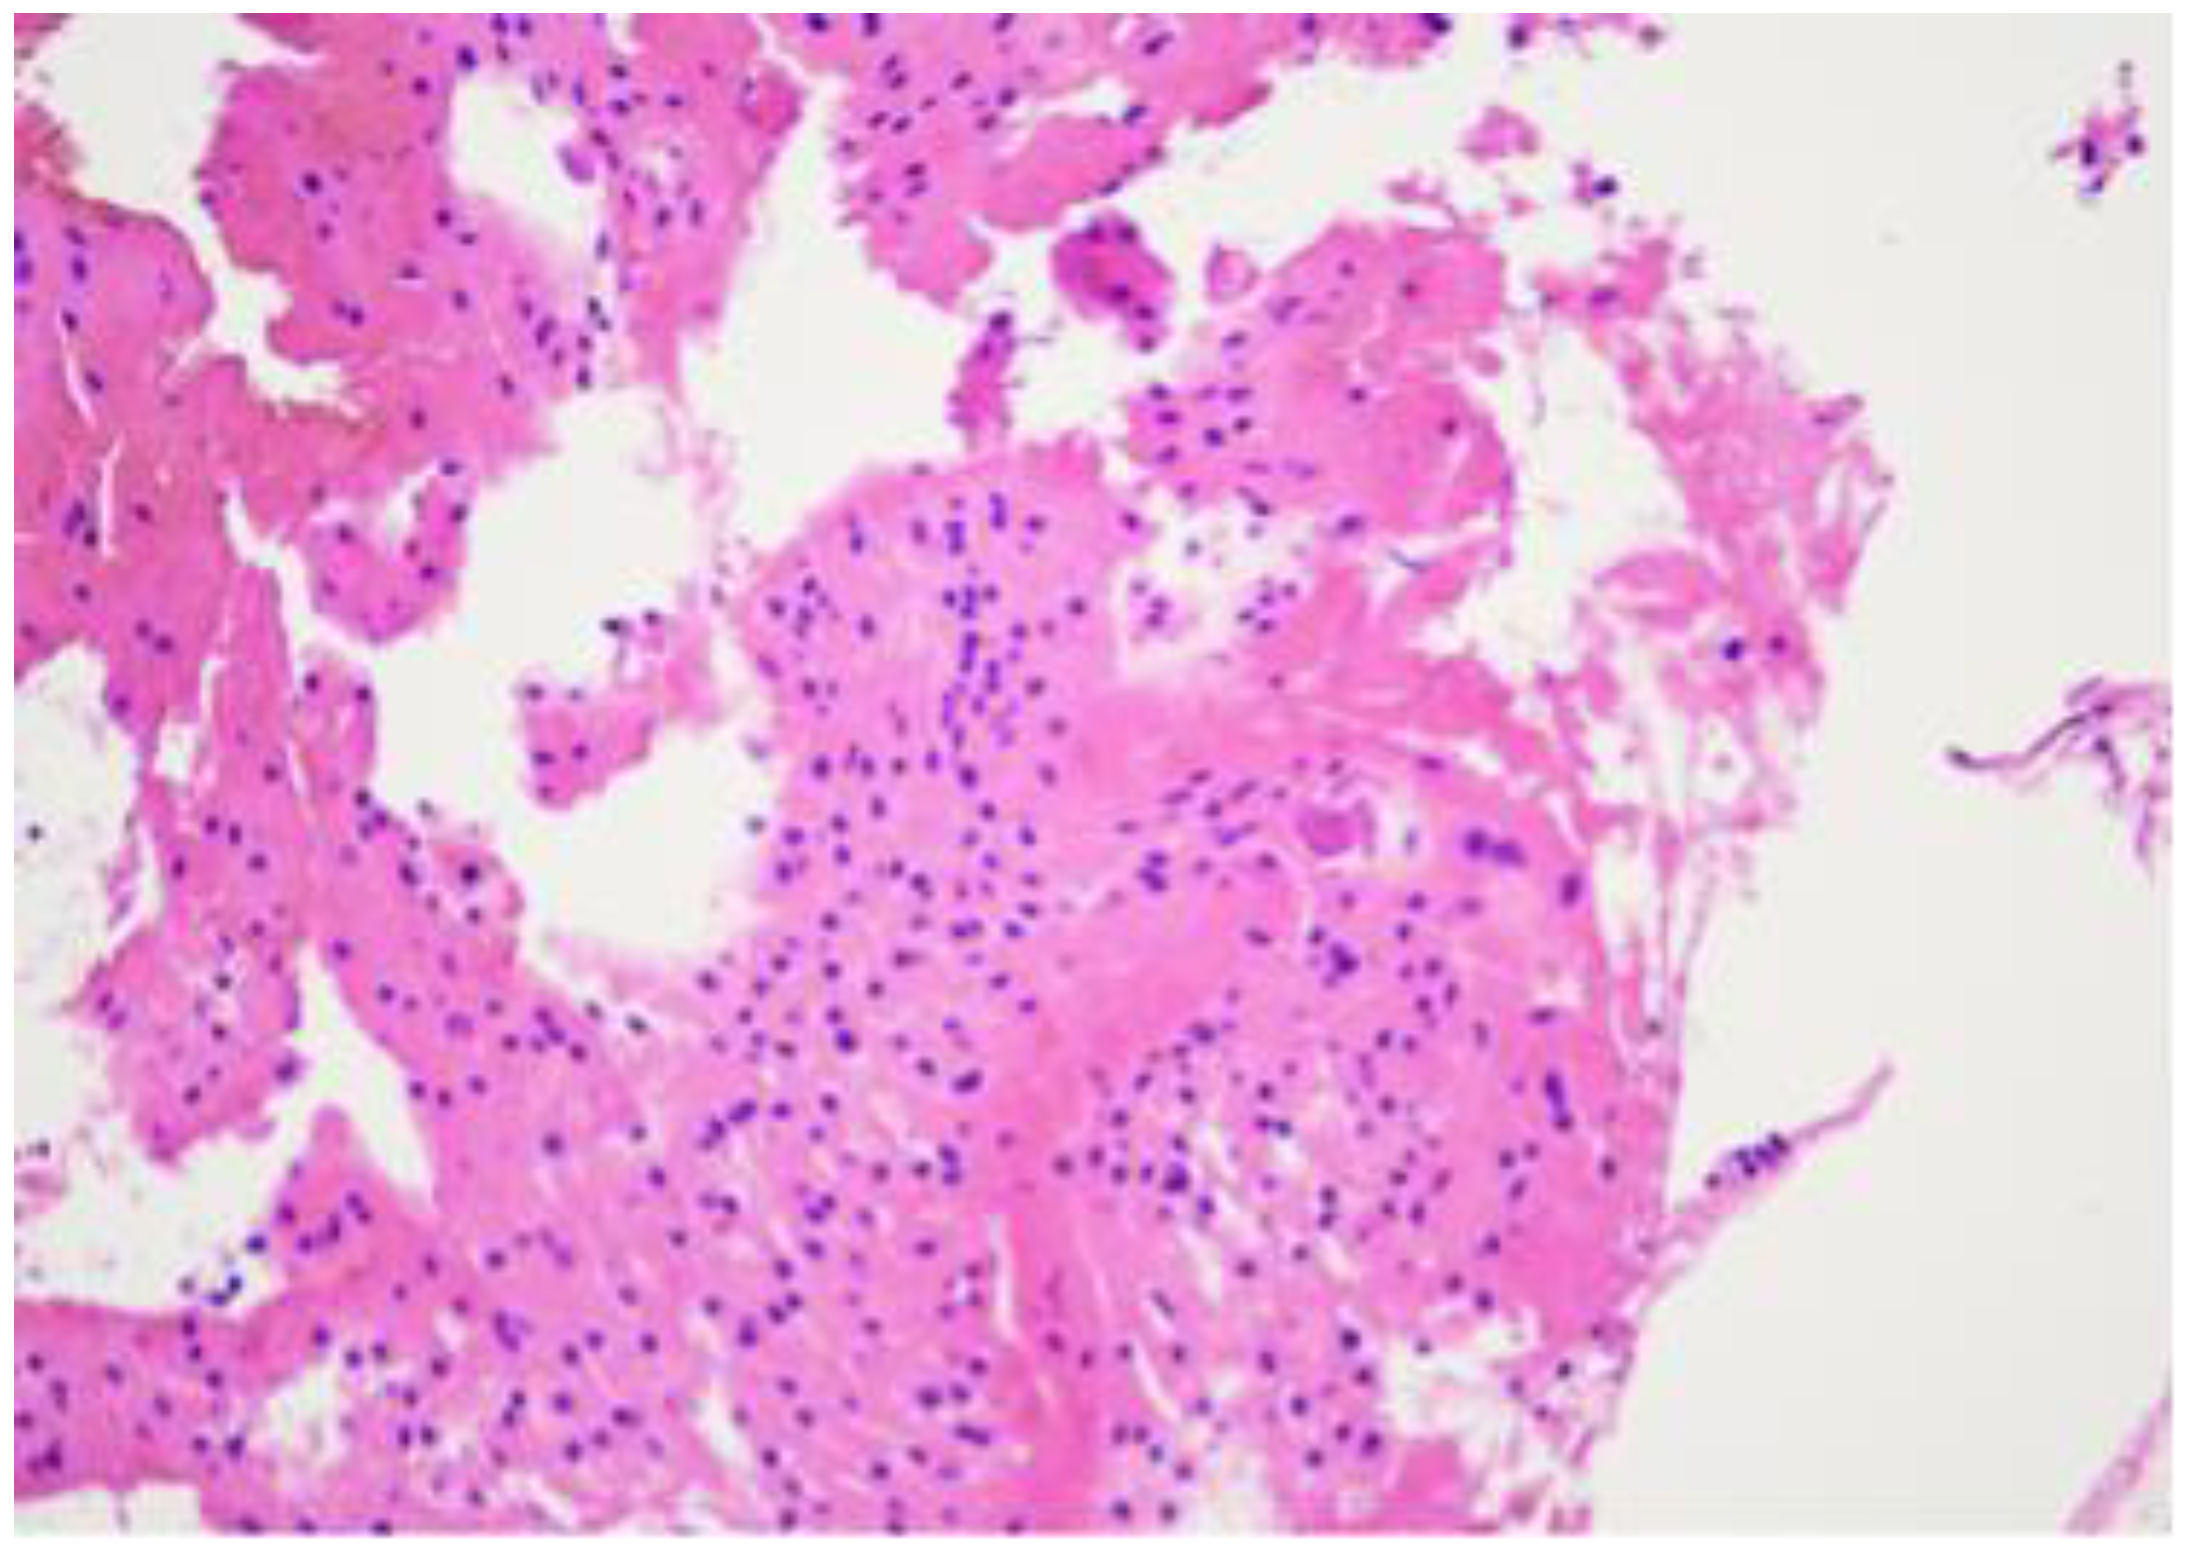

H&Ex10. A bone tumour consists of solid sheets of vacuolated cells with bland round nuclei.

Figure 7.

H&Ex20. A bone tumour consists of solid sheets of vacuolated cells with bland round nuclei. The tumour cells mimic mature fat or brown fat cells. No intracellular myxoid matrix, and no necrosis or mitotic figures.

Figure 8.

H&Ex10. A bone tumour consists of solid sheets of vacuolated cells with bland round nuclei. The tumour cells mimic mature fat or brown fat cells. No intracellular myxoid matrix, and no necrosis or mitotic figures.